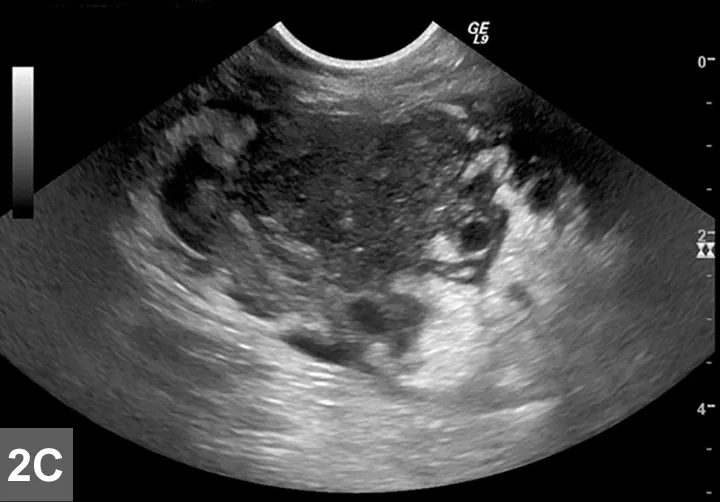

FIGURE 1

EATL type II (small cell) is the most common intestinal LSA in cats (A) and requires immunohistochemical labeling for proper phenotypic characterization and often PARR testing to differentiate from IBD. (B) EATL type I (large cell) occurs less commonly in the small intestine of cats, and neoplastic cells are often large granular lymphocytes. (C) Diffuse large B-cell lymphomas (DLBCL) occur most commonly in the stomach of cats or may present as part of multicentric disease. Although LSA diagnosis is usually made with routine microscopic examination, immunohistochemistry is required to accurately differentiate EATL type I from DLBCL (magnification 40×). Image and description courtesy of Matti Kiupel, Dr. vet. med. Habil, MS, PhD, DACVP, Michigan State University.

• Enteropathy-associated T-cell LSA (EATL) type I (high-grade or large cell/lymphoblastic GI LSA)1,6-7

• Typically involves more intermediate to large cells that display transmural invasion and often form masses (Figure 1B).

• Intermediate to large B-cell LSAs, including diffuse large B-cell  lymphoma (DLBCL), also occur with slightly less frequency (Figure 1C).

• Large granular LSA (LGL)—an aggressive subtype of EATL type I—is comprised of either cytotoxic T-cells or NK cells and characterized by multiple masses within the GI tract and other organ systems.8

• EATL type II

• The more common presentation of GI LSA characterized by diffuse superficial (mucosal/lamina propria) infiltration of small T-lymphocytes that often display epitheliotropism (Figure 1A).1,5-7

• Referred to as low-grade, lymphocytic, small cell, or indolent GI LSA, and associated with a slowly progressive disease course.1,5-7